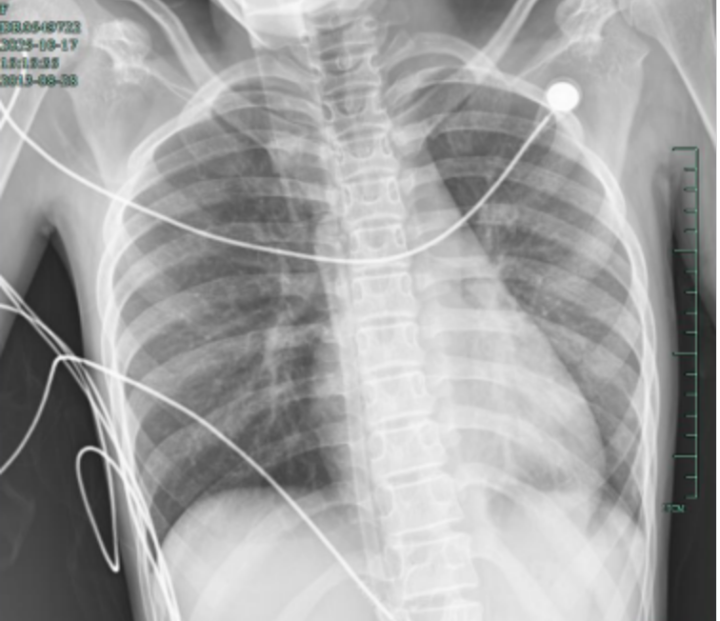

治疗前,左肺呈“白肺”状态

入院后,她很快出现呼吸急促、胸闷胸痛,只能靠5L/min的面罩吸氧维持血氧,胸片显示左肺已完全呈 “白肺” 改变,肺部炎症进展迅猛。